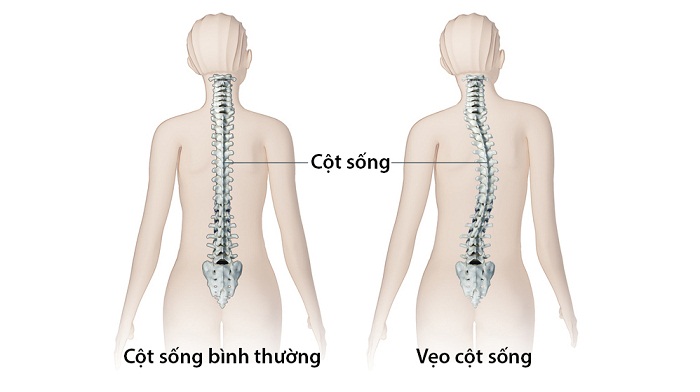

Phục hồi chức năng sau phẫu thuật chấn thương chỉnh hình - cột sống